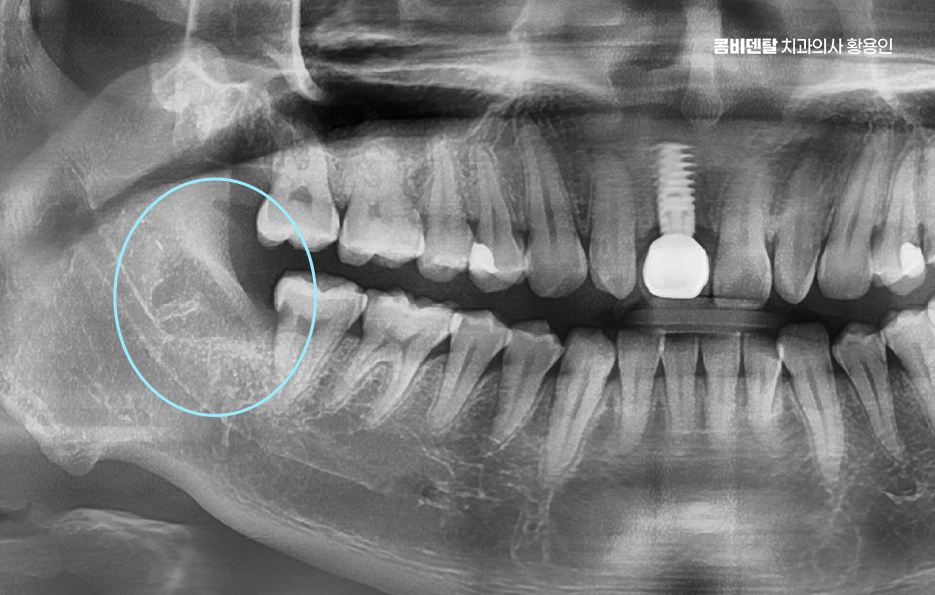

출처 아카이브 열기얼마 전부터 오른쪽 아래 어금니 근처가 묘하게 불편했어요, 처음에는 그냥 음식물이 좀 더 자주 끼는 것 같다고만 생각했는데, 어느 날부터 양치할 때 그쪽을 닦으면 묘하게 시큰한 느낌이 들었어요, 아프다고 할 정도는 아닌데 묘하게 예민하고, 시린 듯도 하고, 찜찜한 기분이 남아서 괜히 그쪽은 피해서 양치하게 되고, 그러다 보니까 오히려 더 불결하게 관리된 게 아닐까 싶은 걱정도 들기 시작했어요, 그렇게 결국 알게 된 사실은 사랑니에 충치가 생겼고, 그 사랑니 바로 앞에 있는 어금니까지 영향을 받아 충치가 함께 진행되었어요. 결국 이렇게 문제가 생기고 나니까 진작 사랑니를 뽑을 걸 하는 후회가 한꺼번에 밀려왔어요 왜 하필 그 끝에 있는 사랑니 때문에 앞에 있는 어금니까지 같이 망가졌을까, 그 어금니는 평생 써야 하는데, 이미 위치 자체가 안 좋은 사랑니 때문에 멀쩡한 어금니까지 문제가 되었다는게 안타까웠어요

이처럼 흔히 사랑니 발치에 대해 무서워서 귀찮아서 뒤로 미루게 되는 경우가 많지만 사랑니의 문제는 단순히 사랑니 뿐 아니라 주변 어금니, 잇몸에도 문제가 이어질 수 있다는 점에서 가볍게 볼 수 없는 문제라고 할 수 있는데요

사랑니 발치 후 충치 치료 그래서 사랑니와 옆 어금니에 충치가 동시에 발견되었을 땐 단순히 사랑니만 뽑고 끝나는 게 아니라, 어금니 충치 치료까지 해야 하는 상황이 발생할 수 있으며 만약 이러한 상황이라면 치료 순서와 계획은 어떻게 세워야 할 지 걱정이 더 커질 수 있는데요.

결론적으로 말하면, 사랑니 발치 후 충치 치료에 있어서 사랑니와 어금니 충치가 동시에 발생했을 때 치료 순서와 방향을 잘 잡는 게 중요하며 단순히 통증 있는 쪽만 치료하는 게 아니라, 원인과 현재 상태를 정확하게 파악하여 치료 계획을 체계적으로 세워야 하며 특히 어금니 충치를 뒤늦게 통증으로 자각하는 경우에는 신경 손상의 가능성이 높아지기 때문에 꼭 아플 때 치과를 방문하는 것만이 아니라 정기적으로 검진하여 사랑니의 발치 시점 및 평소 치아, 잇몸 건강관리에 있어서도 잘 관리하시길 바라고 있어요